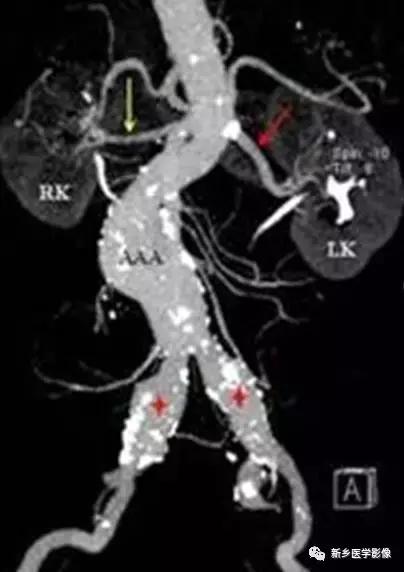

6、动脉钙化动脉瘤